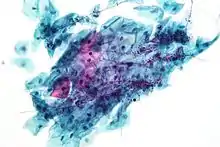

Micrograph of a Pap test showing a low-grade intraepithelial lesion (LSIL) and benign endocervical mucosa. Pap stain.